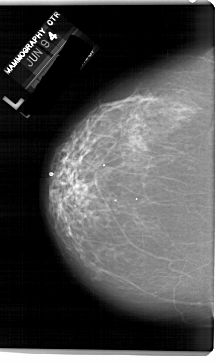

A_1503_1.LEFT_CC

LEFT_CC LINES 6871 PIXELS_PER_LINE 4111 BITS_PER_PIXEL 12 RESOLUTION 43.5 NON_OVERLAY